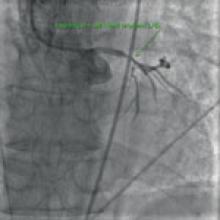

Canada is spearheading an international study to determine if an implantable cardioverter defibrillator (ICD) can prevent death from serious heart rhythm problems in those patients who’ve survived a heart attack. Heart disease is a leading cause of death in Canada and the fastest growing disease worldwide.